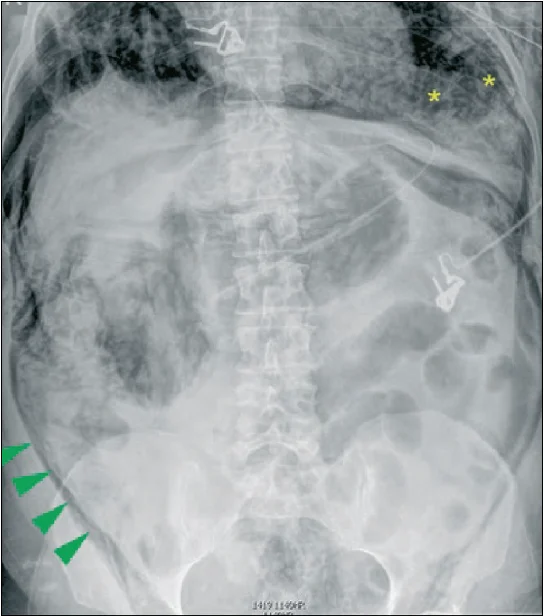

За даними літератури [25], підшкірну емфізему виявляють у 0,3-3,9% хворих (рис. 26).

Рис. 26. Підшкірна емфізема живота (вказана стрілками) [32]